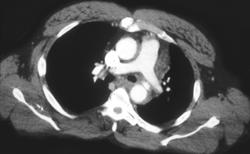

Aortic Dissection